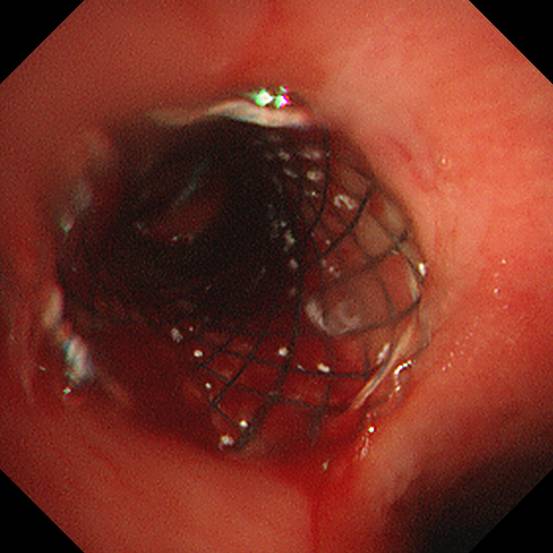

针对患者病情,我院内镜中心介入治疗团队立即组织了病例讨论,在庄武主任和朱坤寿主任支持下,并请有关专家会诊,内镜中心呼吸内镜介入治疗团队经充分论证,为该患者制定了科学的治疗方案——全麻下经硬质气管镜支架置入术,利用覆膜支架覆盖瘘口,从而改善患者症状。

结合胸部CT、气管镜检查所见,根据左主支气管瘘口的范围及程度,团队选取了适合的覆膜气道支架。

在内镜中心护士长、手术室护士长、麻醉科及医院有关职能科室全力配合下,2021年6月18日上午,内镜中心呼吸内镜介入治疗团队完成了本例气道支架置入术,支架置入位置精准,完全贴合瘘口,并且全程仅用时约30分钟。